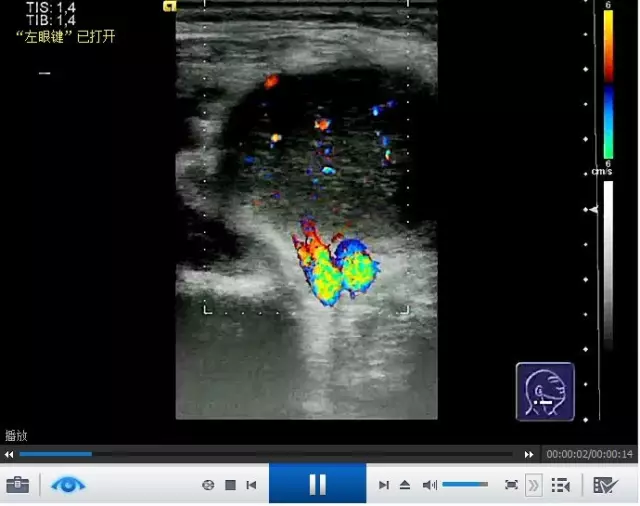

本书由国际著名专家执笔,以图谱形式系统讲解了超声成像原理及其在头颈部病变的诊断和治疗中的应用。该书内容全面,总论与各论并举。全书分为3部分内容,第1部分为总论,内容涵盖了超声成像基本原理、多普勒和彩色多普勒的基本原理、超声检查操作技巧、超声报告与术语。第2部分为超声解剖和病理,分别论述了甲状腺、颈旁淋巴结、颅外神经、口底与口咽、涎腺、面部软组织、喉和下咽、颅外血管病变的超声诊断要点与误区。第3部分为超声新技术及展望,重点论述了超声图像常用处理方法及未来发展趋势。该书内容全面详实,编排体例独特,读者可以分别浏览图片内容和查阅诊断结果。除了书中所呈现的静态图像,本书还配有动态视频内容,清晰的动态影像有助于读者加深对典型超声征象的理解,进一步巩固解剖学知识,提高超声诊断准确率。本书读者面广,可供耳鼻喉科医师、头颈外科医师、颌面部外科医师、放射科医师、内科医师和其他相关专业医师参考阅读。

·本书配有动态视频内容,可供读者进一步深入学习。